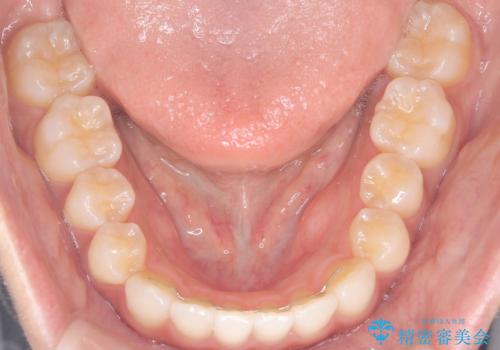

前歯の叢生を非抜歯で改善|インビザライン+IPR・遠心移動・FIX保定

- 前歯部のガタガタ(叢生)を非抜歯で改善するため、インビザラインによるマウスピース矯正を計画しました。抜歯は行わず、歯間をわずかに削るIPR(ディスキング)と奥歯を後方に移動させる遠心移動を併用して、歯を並べるスペースを確保します。歯列が整った後は、FIXリテーナー(固定式保定装置)で後戻りを防止し、安定した歯並びを維持します。

歯を抜きたくないというご希望に応え、インビザラインを用いて非抜歯で歯列を整えました。前歯に必要なスペースを確保するため、歯間をわずかに削るIPRと奥歯を後方に移動する遠心移動を組み合わせました。これにより自然で美しい歯並びを実現。治療終了後は、歯の裏側に目立たないFIXリテーナーを装着し、歯列の後戻りを効果的に防ぎました。患者様は治療中も審美的にストレスなく過ごされ、満足度の高い結果を得られました。